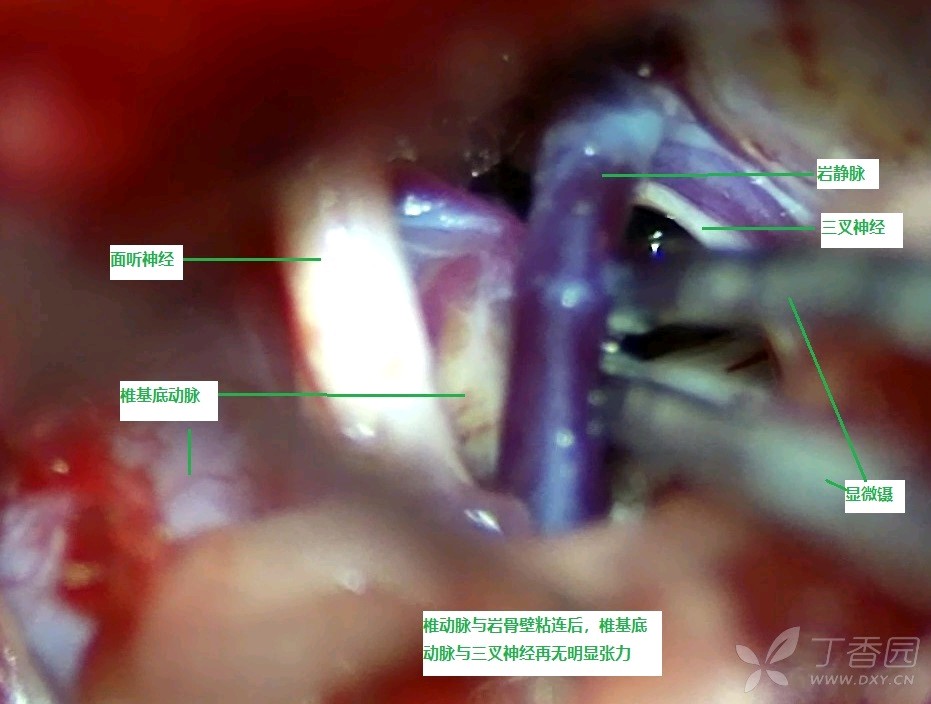

探查见三叉神经中远段仍然受血管压迫,向前下推移虽可离开三叉神经,但因张力极高,直接在神经间垫入Tefflon棉显然不能解除压迫(见图10)。同时因血管巨大,行套索存在困难,遂将血管向下外推向岩骨壁并离开三叉神经,于基底动脉与岩骨壁间注入粘合胶,使椎基底动脉粘附于岩骨壁(见图11、12)

图11 于基底动脉与岩骨壁间注入粘合胶

图12 注入粘合胶后,椎基底动脉粘附于岩骨壁

探查见发现椎基底动脉对三叉神经不再构成压迫(见图13)

图13 椎基底动脉粘附于岩骨壁并离开三叉神经